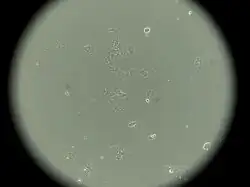

MCF-7 es una línea celular de cáncer de mama que fue aislada en 1970 a partir de una mujer de 69 años.[1] El nombre MCF-7 proviene del acrónimo Michigan Cancer Foundation-7, en referencia al instituto de Detroit donde Herbert Soule y sus colaboradores establecieron la línea celular en 1973.[2] Actualmente, la Michigan Cancer Foundation se conoce como Barbara Ann Karmanos Cancer Institute.[3]

Antes del desarrollo de MCF-7, los investigadores del cáncer no habían logrado establecer una línea de células mamarias que pudiera sobrevivir más de unos pocos meses.[4]

MCF-7, junto con otras dos líneas celulares de cáncer de mama, T-47D y MDA-MB-231, representa más de dos tercios de los estudios sobre líneas celulares de cáncer de mama, según una encuesta basada en Medline.[7] MCF-7 se utiliza ampliamente como modelo en el desarrollo de nuevos agentes terapéuticos, incluyendo fármacos anticancerígenos, estudios de resistencia a antiestrógenos y el diseño de fármacos antiplaquetarios.[8]